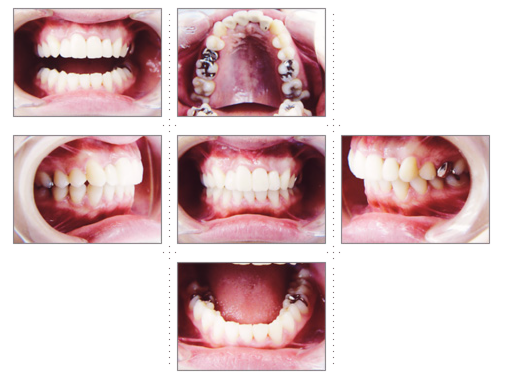

症例3

23才 女性

沖縄のリゾートホテルへ就職が内定している為、通院できるのは4ヶ月という条件で来院。

すべて、3ヶ月で完成し、出発されました。明るい笑顔で接客されていることと思います。